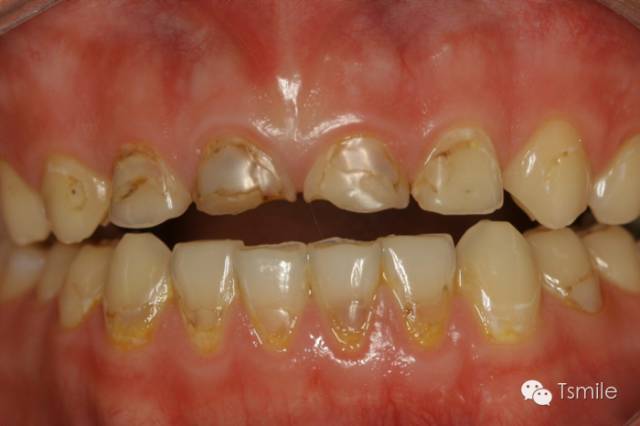

圖1: 夜磨牙導(dǎo)致的牙列重度磨耗

磨耗患者中還有一類特殊的局限于上下前牙區(qū)的牙齒重度磨耗,表現(xiàn)為上前牙舌面、下前牙切端和唇面的重度磨耗。該類患者常表現(xiàn)為一類特殊的咬合類型,重度深覆頜或者上前牙明顯舌傾,這種咬合類型導(dǎo)致下頜前伸功能運(yùn)動(dòng)受限,從而導(dǎo)致前牙區(qū)重度的磨耗,可稱為前牙功能范圍受限(restricted envelope of function)。

圖2: 前牙功能范圍受限導(dǎo)致的前牙重度磨耗